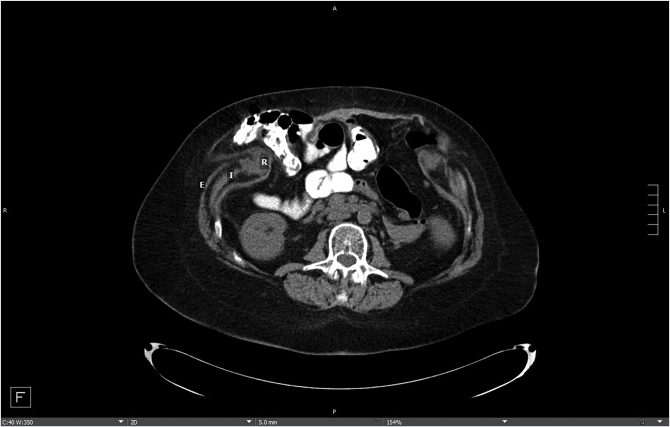

Patient presentation is straightforward, and the majority of diagnoses can be established with a history and physical examination that will distinguish between two conditions—bulges and hernias. Bulges occur when the strength and elasticity of the abdominal wall is not enough to contain the viscera uniformly from episodes of increased intra-abdominal pressure. The classic appearances of postpartum women and the epigastrium of heavier older males (the so-called “beer belly”) are consistent with rectus diastasis and bulges. In general, there is no risk to abdominal wall bulges, because the intestines face a smooth peritoneal lining without abrupt transitions and will not strangulate. In certain areas of the body such as the groin, umbilicus, and the epigastrium, a failure of the local tissue to contain the viscera creates a true hernia–distinctive from abdominal wall bulges due to a small defined ring that can permit entry of a bowel loop and possibly lead to strangulation. In contradistinction to the smooth peritoneal contour of bulges, these “ventral” hernias (as they are located on the front surface of the abdomen) have rings in the shape of the letter omega with a lip that can catch the preperitoneal fat and bowel. A third category of abdominal wall defects is incisional hernias, notable for the scar demonstrating a prior entry into the abdomen (Fig. 41‑1). The scar at the STI has not withstood the abdominal wall tensions and pressures and has failed over time. Mechanistically, the total strength of the physical construct of repair and the biologic healing is less than the loads applied at some point in the postoperative period, leading to deformation of scar and failure. There is some minor overlap between groups; for instance, a bulge from rectus diastasis can be associated with the development of a true umbilical or epigastric hernia. History and physical examination is typically adequate to differentiate these clinical entities, though an abdominal CT scan can add confirmatory information for heavier patients (Fig. 41‑2, Fig. 41‑3).